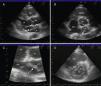

On return to the CCU, the patient experienced complete relief of chest pain and ST-segment normalization on the ECG. Nonetheless, her oxygen saturation level was still 90% despite high-flow oxygen by mask. A full transthoracic echocardiogram examination was then performed. A mass consistent with a thrombus was noted in the left atrium, appearing to arise from a redundant interatrial septum, while the right ventricle was moderately dilated with positive McConnell sign and the interventricular septum was displaced into the left ventricle, which was D-shaped in short-axis view (Figure 3). The pulmonary artery was dilated and the flow across the pulmonary valve suggested severe pulmonary hypertension with pulmonary artery systolic pressure estimated at 70 mmHg. In apical 4-chamber view, color flow imaging of the interatrial septum showed a right-to-left shunt. It was then decided to perform transesophageal echocardiography (TEE) to better characterize the relationship of the mass with the interatrial septum and its embolic potential, and also to look for masses in the right atrium. TTE showed a long thrombus that appeared to be attached to the atrial septum in the region of the foramen ovale. Color flow imaging was consistent with a patent foramen ovale (PFO) and the atrial septum was aneurysmatic. The thrombus had a snake-like movement inside the left atrium and its distal end was freely mobile, prolapsing through the mitral valve (Figure 4). No mass was observed in the right atrium or pulmonary arteries. Thoracic computed tomography angiography revealed bilateral thrombi in the main and lobar branches of the pulmonary artery (Figure 5).

(A) parasternal long-axis view; (B) parasternal short-axis view of the aortic valve; (C) zoom of short-axis view; (D) D-shaped left ventricle. Ao: aorta; IVS: interventricular septum; LA: left atrium; LV: left ventricle; RA: right atrium; RV: right ventricle; RVOT: right ventricular outflow tract; Tr: thrombus.